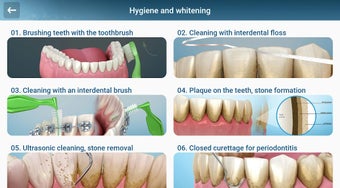

إذا كنت متخصصًا في طب الأسنان أو مريضًا، فقد تساعدك هذه الأداة في تعلم علاجات الأسنان.

يستند التطبيق على مبدأ عرض الشرائح. يحتوي كل موضوع على 3-9 صور. يمكن عرض صور أي موضوع في أي وقت.